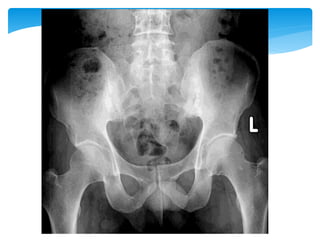

2~5年 Modified New York criteria 1984

1. 下背痛僵硬 休息無法減輕 三個月以上

2. 腰椎活動範圍受限

3. 擴胸範圍受限

4. X光有薦腸關節炎雙側2級或單側3級以上 4+ 1

or 2 or3